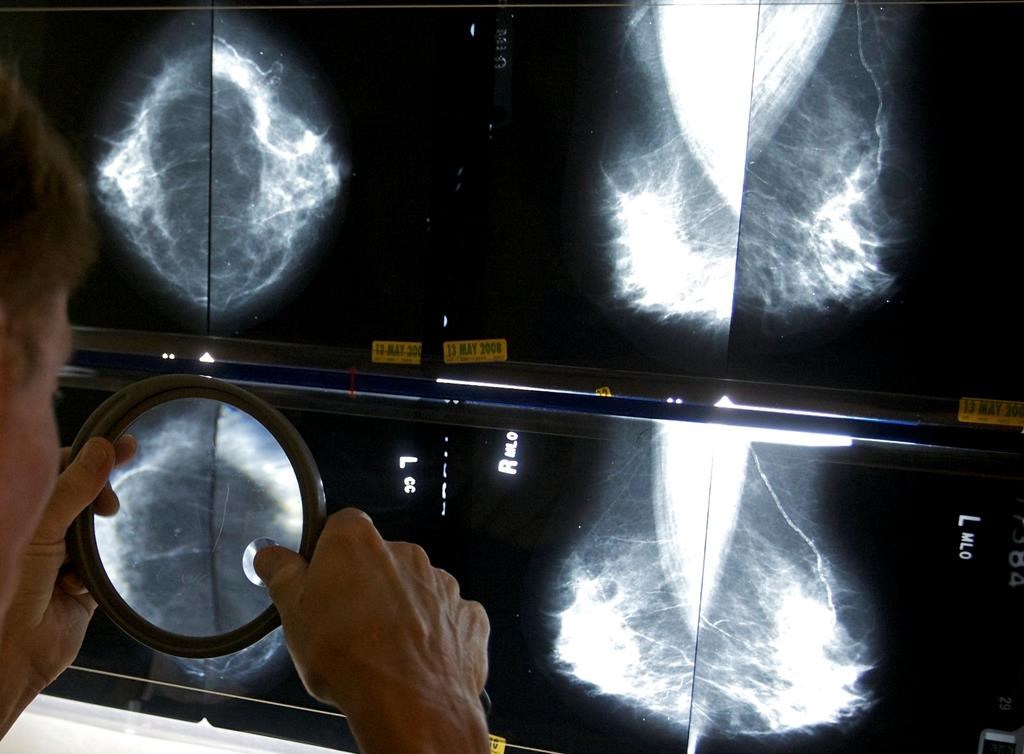

Regina’s Breast Health Centre will provide a co-location of services, such as diagnostic imaging, consultation with specialists and surgeons, patient education, support and navigation. The centre will also offer on-site access to post-treatment care, such as therapies and rehabilitation.

“The Breast Health Centre will provide a central resource for patients who are being investigated for, or have been diagnosed with, breast cancer,” said Sheila Anderson, the SHA VP of Integrated Regina Health.

“The centre will provide advanced imaging, breast biopsy, pre-surgical and post-surgical care all in one place, enhancing the coordination of care for patients and helping health care providers collaborate in providing care to ensure a more respectful and timely experience for the women in their care.”